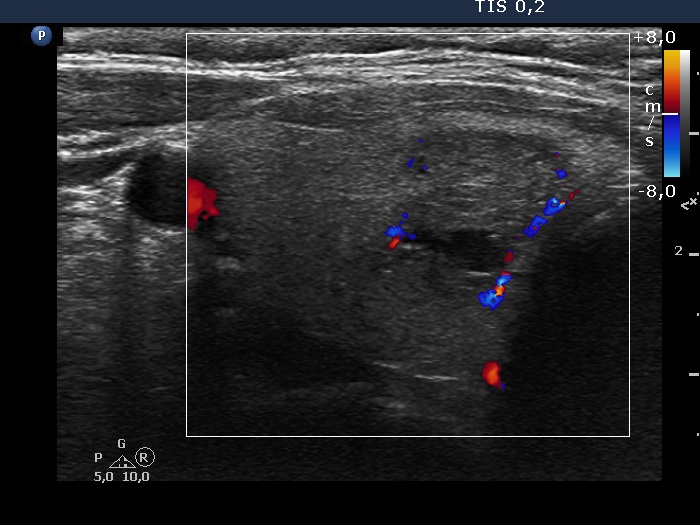

Right lobe, longitudinal scan

Right lobe, transverse view, color Doppler mode. The lesion presents signs of perinodular blood flow.